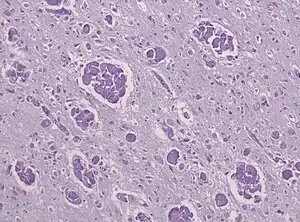

| A histopathology slide of a brain with Krabbe disease showing giant cells with PAS stain inclusions ("globoid cells") within astrocytic gliosis and loss of myelinated fibers. | |

The disease may be diagnosed by its characteristic grouping of certain cells (multinucleated globoid cells), nerve demyelination and degeneration, and destruction of brain cells. Special stains for myelin (e.g., luxol fast blue) may be used to aid diagnosis.